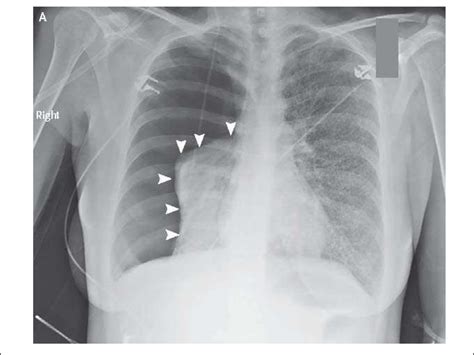

Pneumothorax

Пневмоторакс (Pneumothorax) - ErdeMED